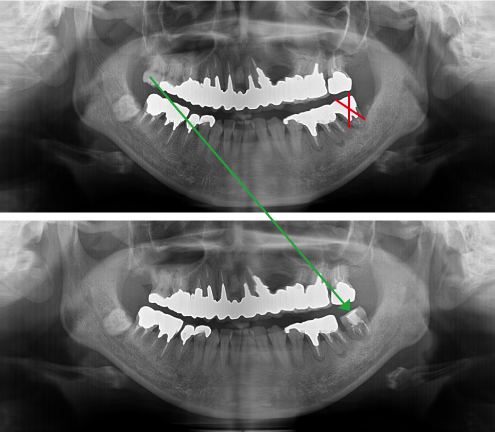

根管治療BEFORE・AFTER

虫歯治療